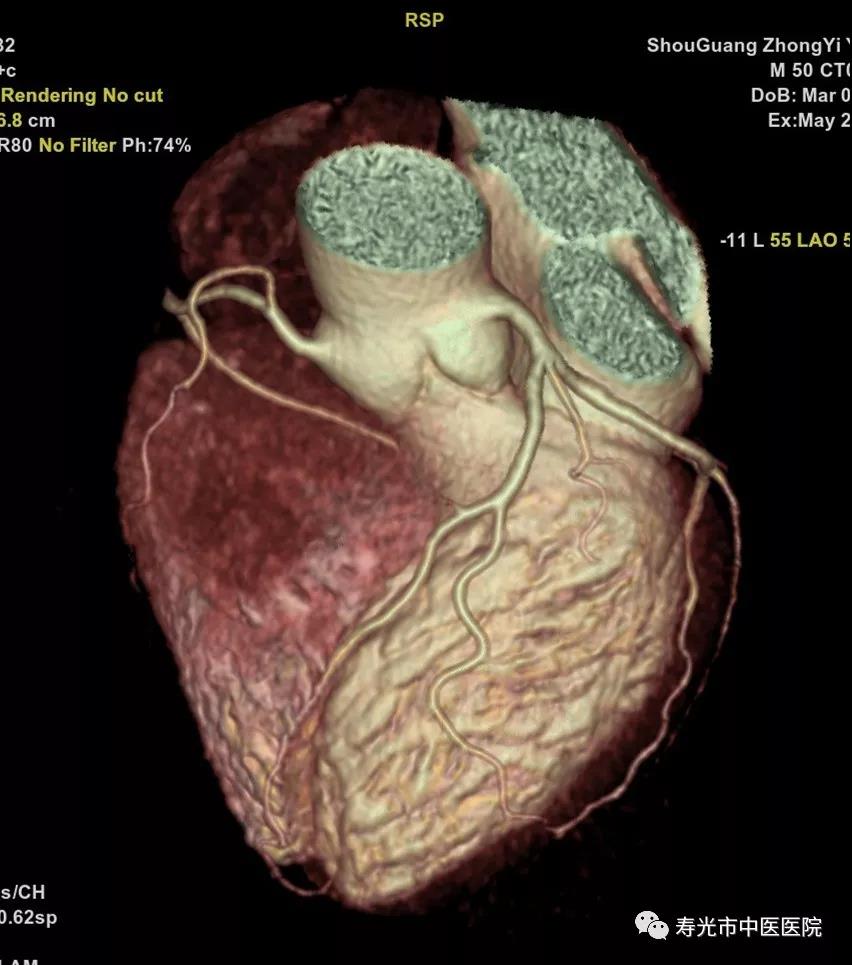

CT检查:清晰成像 挑战重疾

256排Revolution CT被称为“革命型CT”、“CT界的航母”,融合超高端CT的能谱扫描、高时间分辨率扫描和宽体探测器扫描三个领域顶尖科技于一身,实现了无限制1-Beat心脏成像、无限制1-Stop脑卒中成像、多通道主机能谱成像,打造了CT覆盖范围、速度、图像质量、辐射剂量、能谱和扫描舒适性的业界新典范,建立了心血管、神经、肿瘤、呼吸系统、泌尿系统及骨科专业等疾病的成像和低剂量筛查领域全新标准,大幅提高医疗效率和患者体验,有效协助医生进行精准诊断和应对重疾挑战。

如今胸痛病人比较多见,而胸痛确诊需要“排除法”,传统的检查方法是分别做肺动脉、胸主动脉和冠脉的造影,一一排除之后,发现病灶,每次检查都要为患者注射一次对比剂。而使用这台仪器,只需注入一次对比剂,就能完成对这三个部位的检查,实现三联扫。“这给胸痛中心和急性胸痛病症的检查流程改善带来了福音。”

领先之处不仅在此,在做冠脉成像的时候,传统检查需要药物降低患者的心率,使用这台机器,不需要控制心率,只需患者心脏搏动一次,用0.28秒的时间就可以完成。“即使心率不齐的患者,也可以通过这台仪器进行检查。”

CTA成像

CT下冠脉CTA 3D成像